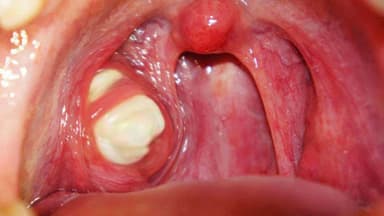

Amidan sản sinh ra kháng thể và có chức năng bảo vệ cơ thể chống các vi khuẩn xâm nhập qua đường ăn và đường thở. Tuy nhiên do có cấu trúc nhiều hốc, ngăn nên giống như một hạch bạch huyết nghĩa là có nhiều múi, chia nhiều ngăn tạo thành các hốc nên thức ăn và vi khuẩn dễ xâm nhập gây viêm. Vi khuẩn khi xâm nhập ẩn náu lâu ngày trong các hốc amidan tạo nên các khối mủ bã đậu, vón cục.

Trẻ em là đối tượng rất dễ bị viêm amidan, trong đó có viêm amidan hốc mủ. Nếu bé bị viêm amidan mủ kéo dài sẽ gây hơi thở hôi và xuất hiện các biến chứng quanh amidan rất nguy hiểm. Do đó cần được điều trị sớm bệnh cho bé.